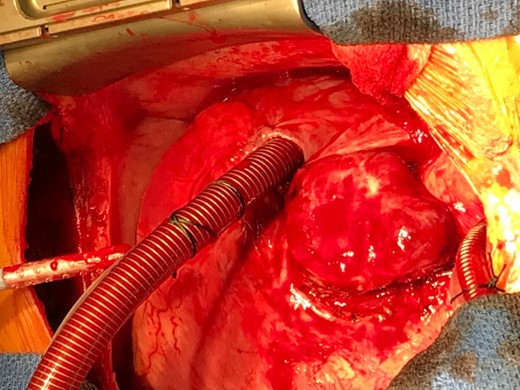

Pre-operative planning suggested thoracic dissection was technically feasible without cardiac bypass. However, during resection of the tumour, it was found to be densely adherent to the right ventricular surface in the aorto-pulmonary window (Fig. 3). Tumour excision caused a ventricular perforation with bleeding controlled by digital pressure. To minimize haemorrhage from the ventricular perforation and to fully excise the tumour from the origin of the right coronary artery, cardiopulmonary bypass was rapidly instituted and maintained for 44 minutes. After commencing the bypass, the patient’s blood pressure dropped rapidly from 80/40 mmHg to 30/20 mmHg. Large doses of norepinephrine, phenylephrine and metaraminol were administered to improve hypotension and pump pressure, but there was little effect due the catecholamine resistance from phenoxybenzamine alpha blockade. Adrenaline and fluids were then given and the blood pressure eventually responded and stabilized. Thereafter, the thoracic component of the tumour was successfully fully excised.

Macroscopic appearance of the specimen, showing a large, well defined and highly vascular tumour located at the aorto-pulmonary window.